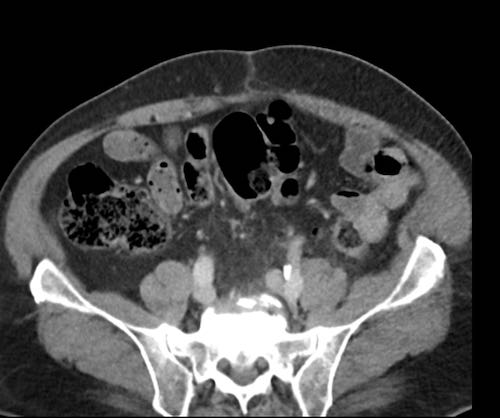

Ca lâm sàng 2

Cuộn qua các lát cắt.

Bạn có thể phát hiện tất cả các tổn thương cấy ghép phúc mạc không?

.jpeg)